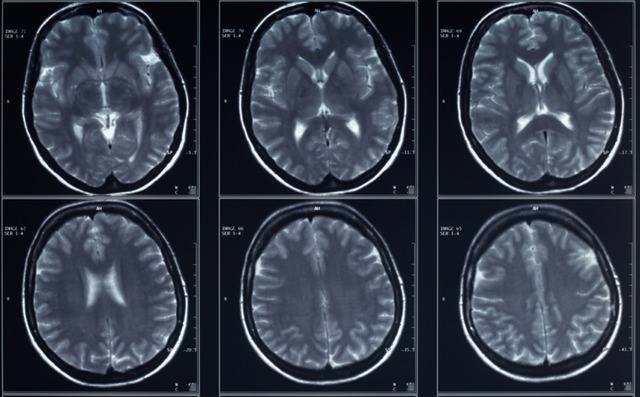

生活習慣病を抱えていたり高齢である場合は、ウイルスが破壊した血管で形成される血栓に対して脳は脆弱になり、脳梗塞を起こしやすくなる/Credit:富士脳障害研究所附属病院

上にあげたように、複数の研究でウイルスが脳にダメージを与えることがわかりました。

ウイルスが脳へダメージを与える仕組みとして考えられているものには、次の3パターンが存在します。

1つ目は、ウイルスが血管に感染したことで血管が損傷して血栓を生成され、それが脳血管をつまらせた可能性です。

これは現在最も広く知られている事例です。特に生活習慣病をもつ人や高齢者など、血管が弱っている人はウイルスの血管に対する攻撃に脆弱で、より多くの血栓を生成してしまいます。

画像は人間の壊死を起こした脳。マウスを使った実験では鼻腔の神経を遡ってウイルスが脳に到達したことがわかっている/Credit:Clinical Infectious Diseases